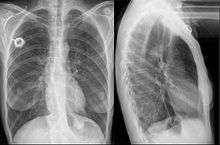

Esophageal stent

An esophageal stent is a stent (tube) placed in the esophagus to keep a blocked area open so the patient can swallow soft food and liquids. Esophageal stents may be self-expandable metallic stents, or made of plastic, or silicone, and may be used in the treatment of esophageal cancer.

As of 2009, covered self-expanding metal stents were the only FDA-approved to be placed permanently. Occasionally, these stents may be placed as part of a clinical trial or as off-label use to repair esophageal leaks or fistulae. They are placed using the guidance of fluoroscopy (x-ray) and endoscopy. Usually, they are left in for less than four weeks.